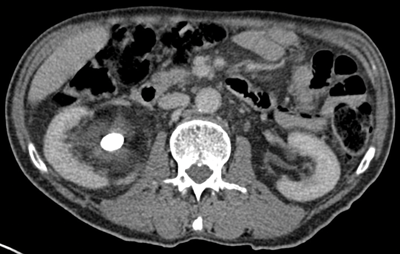

The stone alongside the stent may be masked using abdominal windows, but when changed to bone windows, the stone can be clearly seen due to the difference in HU of the stone compared with the stent (Figure 1) [1].

Figure 1a: Abdominal windows stone and stent.

Figure 1b: Bone windows stone and stent.

This allows a stent or nephrostomy tube to be distinguished from a calculus [2] and can help aid further patient management.